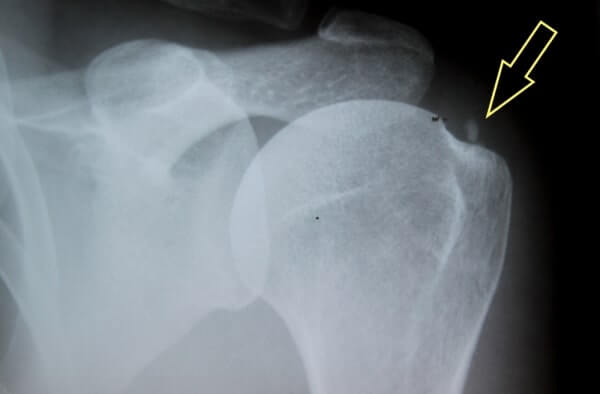

Kako se diagnosticira kalcinacija v rami?

Kalcinacije v rami pogosto prepoznamo po opravljenem rentgenskem slikanju, mamografijah ipd.. Najbolj zanseljiva metoda za diagnosticiranje kalcinacije v rami je ultrazvočna preiskava (UZ) mehkih tkiv. Ultrazvok natančno prikaže lego kalcinacije ter stopnjo degenerativnih sprememb na priležnih vezivnih strukturah.

Ultrazvočna diagnostika se uporablja tudi za spremljanje napredka zdravljenja kalcinacije v rami v sklopu terapij z udarnimi globinskimi valovi. Pri sumu na kalcinacijo v rami se lahko izvede tudi MR diagnostika oz. magnetna resonanca, vendar je najbolj zanesljiv UZ.

Da, ultrazvočna diagnostika je najhitrejša in najučinkovitejša metoda za potrditev kalcinacije rame, saj jasno prikaže velikost, gostoto in natančno lokacijo kalcinata v tetivi rotatorne manšete. Za dopolnitev ocene se po potrebi uporabi rentgensko slikanje, ki potrdi stadij kalcinacije (formativna, resorptivna ali postkalcifikacijska faza).

Klinični pregled pri specialistu fizioterapije, ki vključuje specifične provokativne teste, je potreben za zagotovitev skladnosti med klinično sliko in slikovno diagnostiko. V Medicofit kliniki kombiniramo analizo ultrazvočne diagnostike s funkcionalnim testiranjem gibljivosti in oceno mišične moči, kar omogoča natančno določitev faze bolezni ter pripravo najprimernejšega programa zdravljenja.